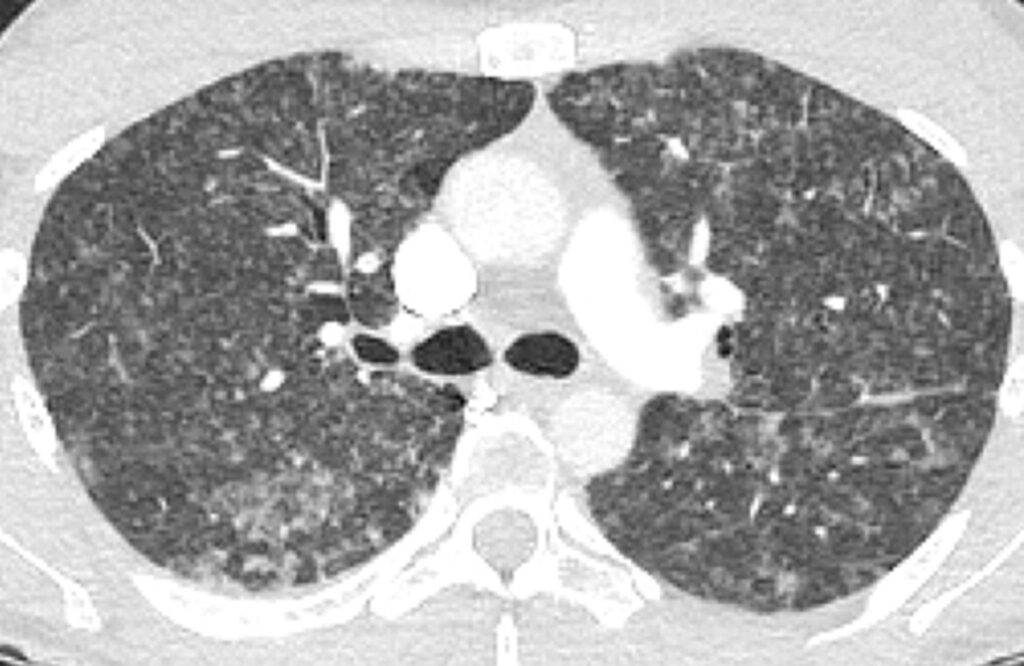

典型的CT所見!

画像は典型的な非線維性HPであり、国家試験や卒業試験でも頻出です。しかし、研修医にもかかわらず診療指針を読み、HPに気づいたB先生はお見事です。

そして最も重要なのは、山ほどある問診項目を丁寧に患者さんに聞き、原因と思しき抗原を特定したことです。典型的画像、肺の病理所見、気管支肺胞洗浄のリンパ球増多などからHPと診断は可能ですが、HPでは原因の特定と排除が何より重要です。

本症例は、若手医療者に「診療指針を読むこと」と「HPにおける原因特定の徹底的問診の重要性」を伝えることを目的としています。今回のエピソードも過去の実例を基に再現したものです。掲載している匿名画像は Respirol Case Rep. 2024 Feb 13;12(2):e01293. より引用しています。